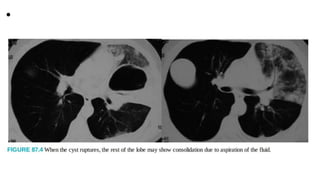

• Clinical findingsdepend on the perforated or intact status, size, location, and invasion and migration of the cysts. Intact cysts may be diagnosed with the symptoms of cough, dyspnea, and chest pain. Ruptured cysts may cause the expectoration of cyst contents, productive cough, fever, repetitive hemoptysis, and anaphylactic shock (Fig. 87.4). Hydatoptysis, or the expectoration of fluid from the cyst or membranous tissues of the cyst, was observed in 29% of the patients in one series.22 Although it has been reported to be a very rare cause of pulmonary nodules, this finding is not uncommon in endemic regions. In fact, in an article published by a Spanish group in the early 1980s, this presentation of the disease has been reported as the most common cause of solitary pulmonary nodules.22 Although the most common findings depend on the studies,

• consolidation adjacent to the cyst (ruptured cyst)